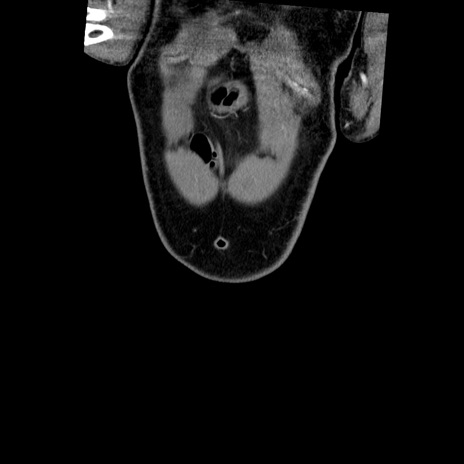

症例22(冠状断像)

【症例】50歳代男性

【主訴】腹痛

【現病歴】AVMからの被殻出血のため回復期リハ病棟入院中。 本日午後3時頃急に下腹部痛が出現した。

【既往歴】AVM、被殻出血、虫垂炎、高血圧

【身体所見】意識晴明、左半身不全麻痺、会話の理解は良好、36.5°C、腹部:膨隆、全体に板状硬、下腹部正中に圧痛点あり、反跳痛-、筋性防御不明、右下腹部にope scar

【データ】WBC 9400、CRP 0.06